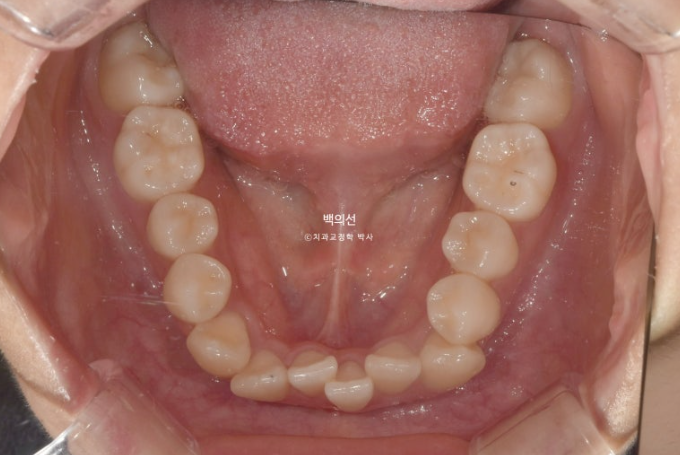

23년 7월 교정을 위해 내원한 환자분입니다.

덧니가 심한 편 입니다.

잇몸이 얇아서 20대 초반의 나이임에도 불구하고 덧니를 포함한 일부 치아의 잇몸이 내려가 있습니다.

군데군데 잇몸이 내려가 뿌리 노출된 부분들이 있습니다.

교정치료로 한 번 내려간 잇몸이 다시 차오르지는 않지만 , 발치교정을 통해 최소한 뿌리를 안쪽으로 넣어주어

더 이상 내려가는 것을 막아줄 순 있습니다.

덧니 펼 공간이 많이 필요하고 잇몸도 얇아 비발치로 치료 시 잇몸이 더 내려갈수도 있는 상태입니다.